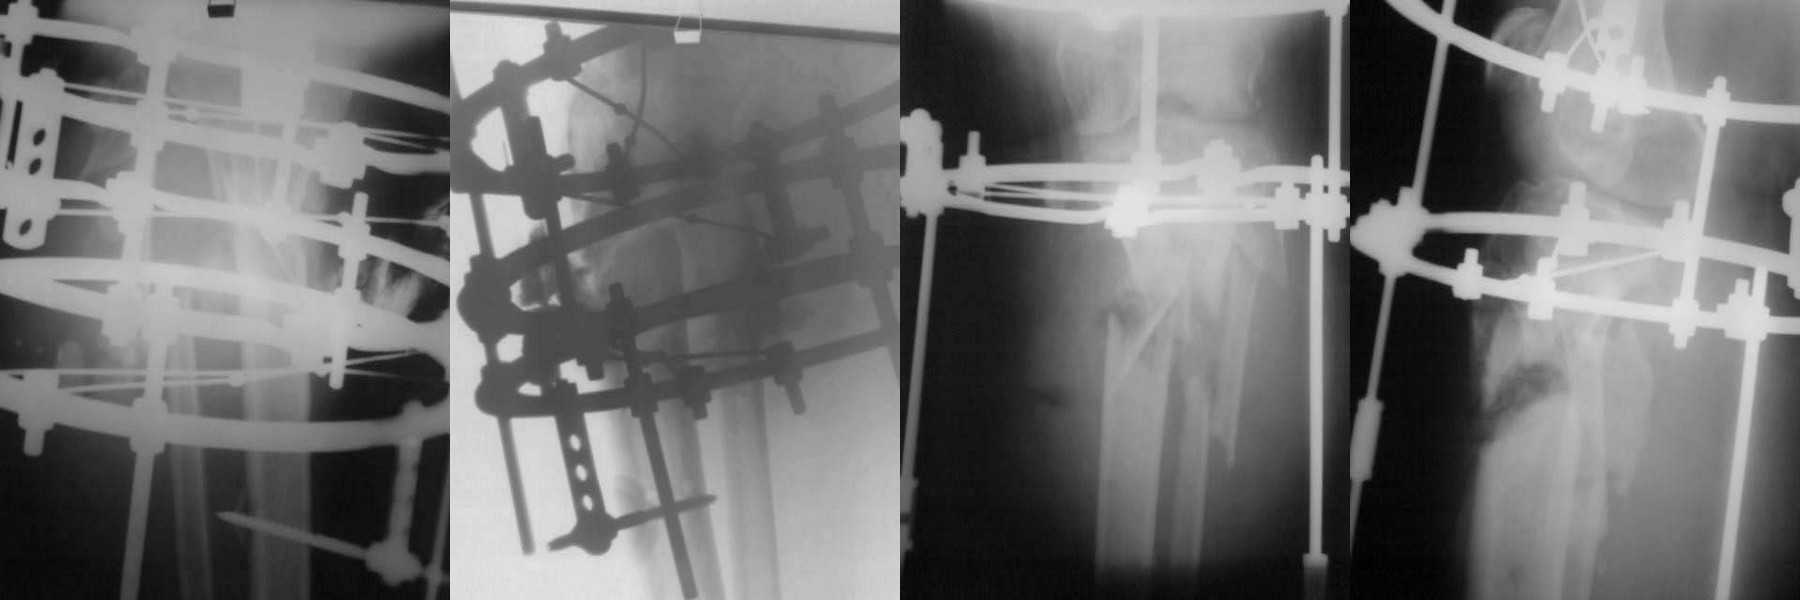

Уважаемые коллеги! Прошу Вашего совета в данной ситуации. Больная 63 лет получила травму в

сентябре 2009 года. Диагноз: Сочетанная травма. ОЧМТ. Ушиб головного мозга легкой степени

тяжести. Травматическое субарахноидальное кровоизлияние. Ушиблено-рваная рана головы.

Закрытый фрагментарный перелом обеих костей левого предплечья со смещением. Открытый 2Б

степени оскольчатый перелом обеих костей правой голени со смещением отломков. Закрытый

перелом малоберцовой кости левой голени в верхней трети со смещением. Рваная рана правой

голени. Нейропатия малоберцового нерва справа, состояние после синтеза правой голени по

Илизарову. Закрытый перелом поперечного отростка L-5 справа. Закрытый перелом боковых

масс крестца с обеих сторон, лонной и седалищной костей справа. Правосторонний

гидроторакс. Правосторонняя пневмония. Бронхиальная астма. Миокардиодистрофия

смешанного генеза, ХСН 1 ф.кл. Варикозная болезнь нижних конечностей. ХВН2 степени.

Остеопороз.

Перенесла несколько операций в условиях ЦРБ и краевой больнице. В настоящий

момент у больной имеется несросшийся многооскольчатый перелом обеих костей правой голени,

хронический остеомиелит, свищевая форма нейропатия малоберцового нерва справа.

04.02.2010г. больной выполнен: перемонтаж аппарата внешней фиксации, иссечение свищей,

секвестрэктомия, дренирование полости. Рана полностью не ушита видна кость, дренаж удален

на 5 сутки, из раны скудное геморрагическое отделяемое, грануляции вялые, местами фибрин,

голень отечна (отек не увеличился и не уменьшился), околоспицевого воспаления нет,

температура тела нормальная, в лабораторных анализах легкая анемия, лейкоцитоза и

палочкоядерного сдвига нет, биохимия и моча норма, в посеве из раны в первом St. Epidermidis,

во втором роста бак. флоры нет. Планируется консервативное лечение до гранулирования раны,

затем замещение костного дефекта аутокостью. Рану не решился сразу зашивать и замещать

костный дефект, в виду имевшегося гнойного затека 4,0х2,0 см. С данной патологией

встретился впервые. Прошу совета по тактике ведения больной. Смущает длительно

сохраняющийся отек и вялое течение заживления. Фото досылаю.